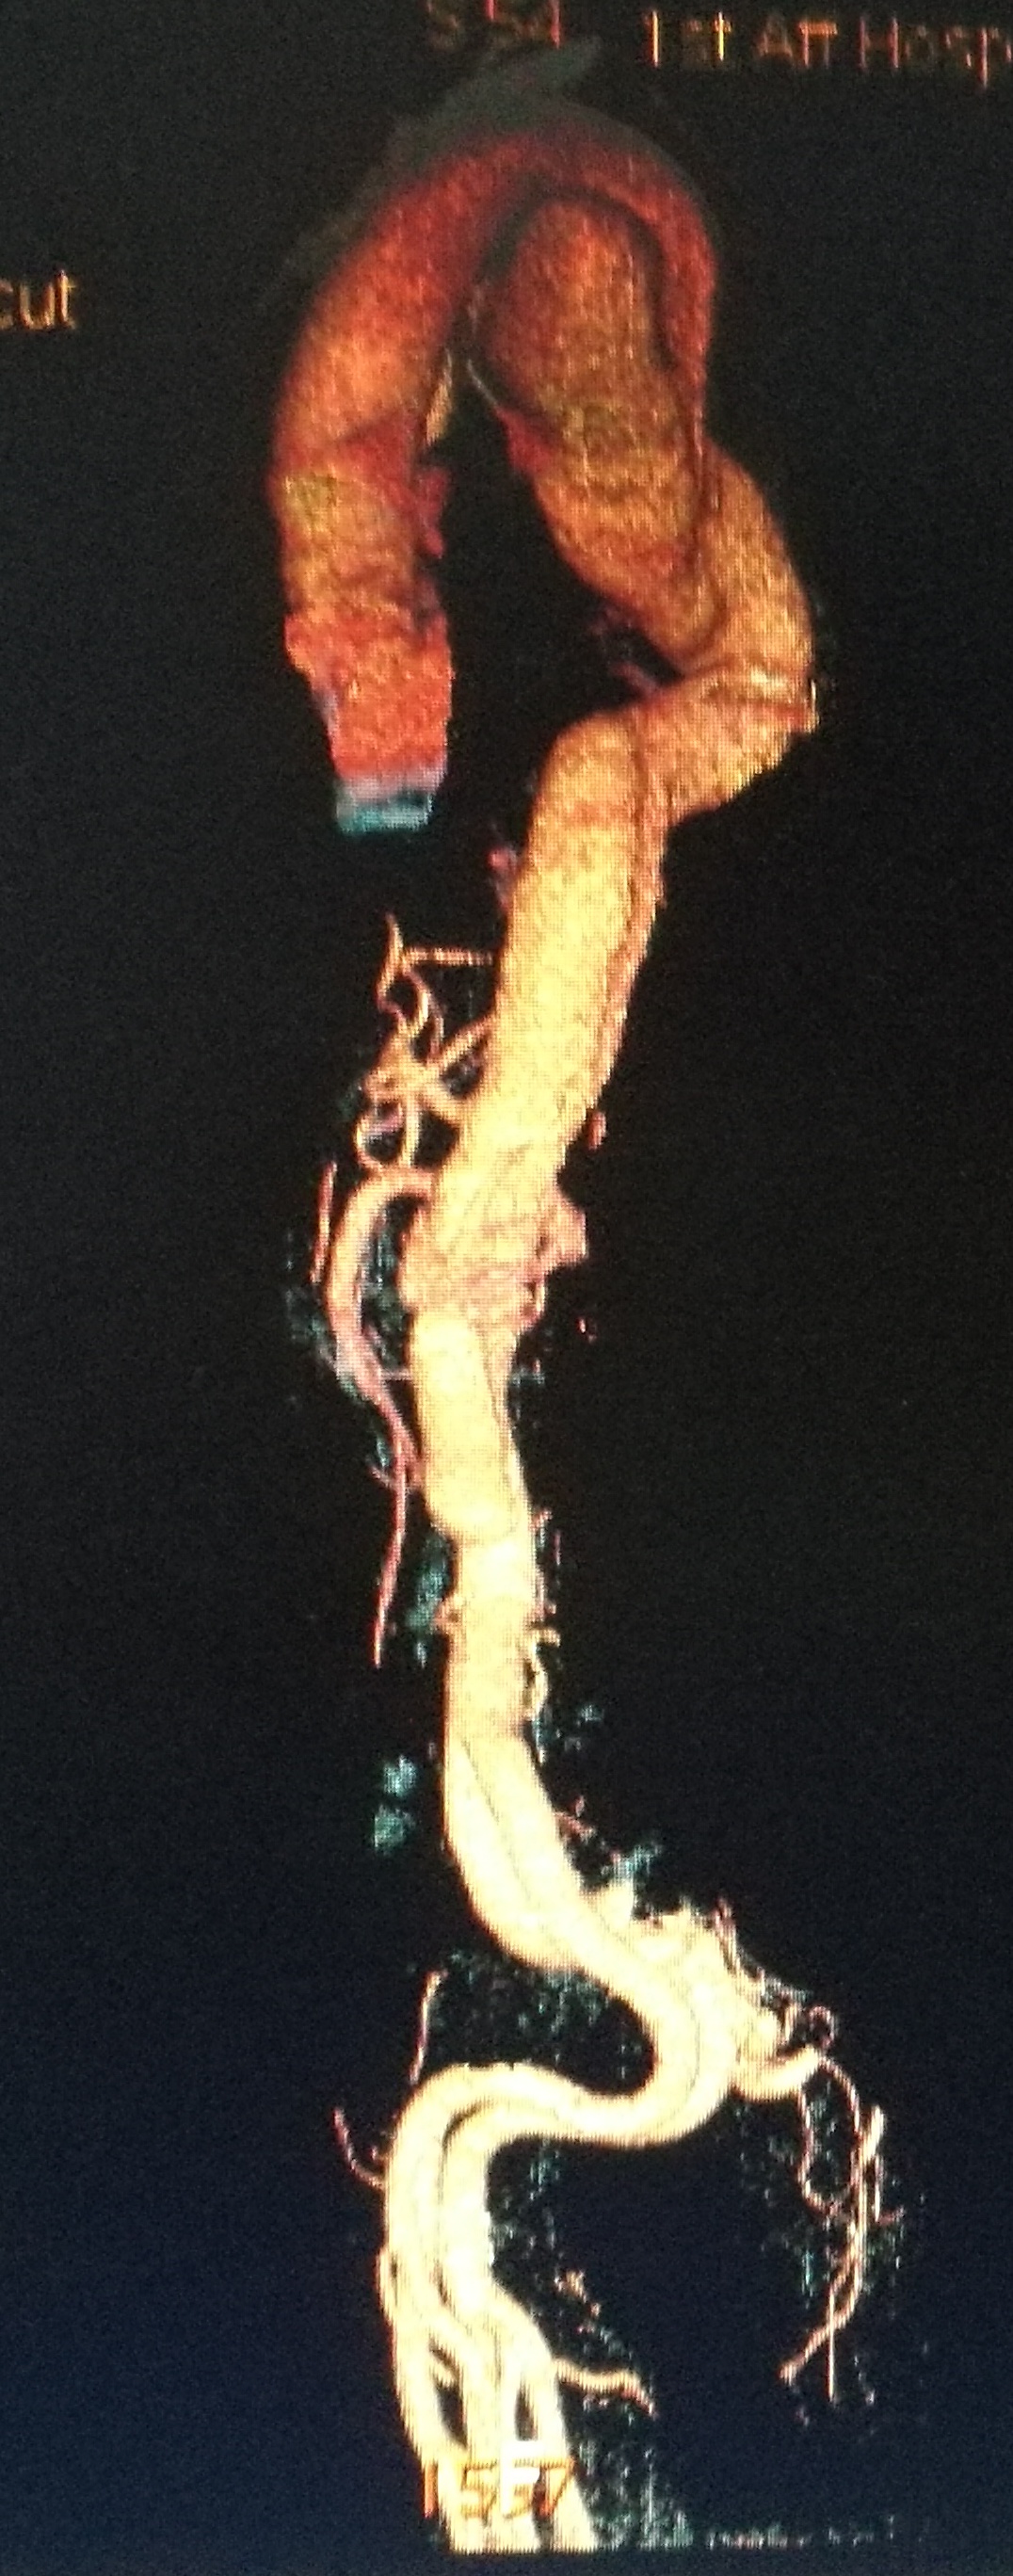

此例患者进行发病时未能确诊,进入慢性期后假腔扩张瘤样变。在CT的部分层面,食道受压看不到。重建影像可见假腔扩张,动脉扭曲。

手术在局麻下进行,经右股动脉穿刺置管到升主,经左桡动脉穿刺植入金标猪尾导管,造影,为确认真假腔,加做右前斜位造影,确认股动脉导管在真腔内,测量后植入覆膜支架。由于扭曲严重(腹主,膈肌附近,弓降),支架最初并未贴服大湾侧,支架送过锁骨下动脉后适当回撤,请拉释放导丝,此时支架整体向大弯侧轻微移动,考虑应力已经得到缓解。完全释放支架,定位良好,封堵完全无内漏。